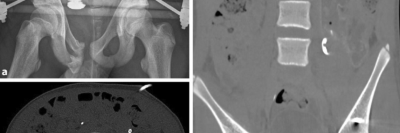

Übersehene Verletzungen in der Kindertraumatologie

Bei mehrfach verletzten Kindern werden trotz moderner Bildgebung häufig Verletzungen übersehen. Somit bleiben sie ein Risiko in der Notfallversorgung. Zwei Fallbeispiele zeigen, wie standardisierte Abläufe, festgelegte Zuständigkeiten und Nachuntersuchungen dabei helfen können, solche Verletzungen frühzeitig zu erkennen.

Bauchhoden/© Springer Medizin Verlag GmbH, Blutung im transversalen als auch im saggitalen Schnitt/© Institut für Diagnostische und Interventionelle Radiologie der Uniklinik Köln; mit freundlicher Genehmigung, Abdomensonographie: 14,7 mm große zystische Struktur im Bereich des rechten Ovars/© Isaev Y et al. / all rights reserved Springer Medizin Verlag GmbH, Röntgen einer Beckenfraktur und Abdomen-CT bei Jugendlichem/© Karvouniaris N. et al. / all rights reserved Springer Medizin Verlag GmbH, Drohende ösophago-arterielle Fistel nach Batterieingestion/© Lohmann J et al. doi.org/10.1007/s00101-024-01477-3 unter CC-BY 4.0, Kleinkind und Teddy mit Verband/© simoningate / Getty Images / iStock (Symbolbild mit Fotomodell), Akute Appendizitis/© Springer Medizin, Kind mit Gipsarm/© nycshooter / Getty Images / iStock (Symbolbild mit Fotomodell), Appendizitis /© Springer Medizin Verlag GmbH, Operationstechnik der Limberg-Plastik bei Sinus pilonidalis/© Jamal Driouch et al., Ärztin und Patientin im Gespräch/© andrei_r / Getty Images / iStock (Symbolbild mit Fotomodell), Bunte Plastikperlen/© Steven White / Getty Images / iStock, Ärztin betrachtet Röntgenbild/© dusanpetkovic1 / stock.adobe.com (Symbolbild mit Fotomodell), Search Icon, Knochensäge im Einsatz bei Knie-TEP/© Issara / stock.adobe.com (Symbolbild mit Fotomodellen), Hirntumoren sichtbar im MRT/© semnic / Getty Images / iStock (Symbolbild mit Fotomodell), Lungentrainer/© S@photo / stock.adobe.com (Symbolbild mit Fotomodell)